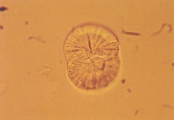

Рис. 25. Микрофотография цистиновых кристаллов в мочевом осадке 2- летнего кобеля английского бульдога с цистиновыми камнями в мочевом пузыре (не окрашено, увеличение Х 250).

Рис. 26. Сканированная электронная микрофотография кристаллов, описанных в рис. 25 (увеличение Х 1,980).